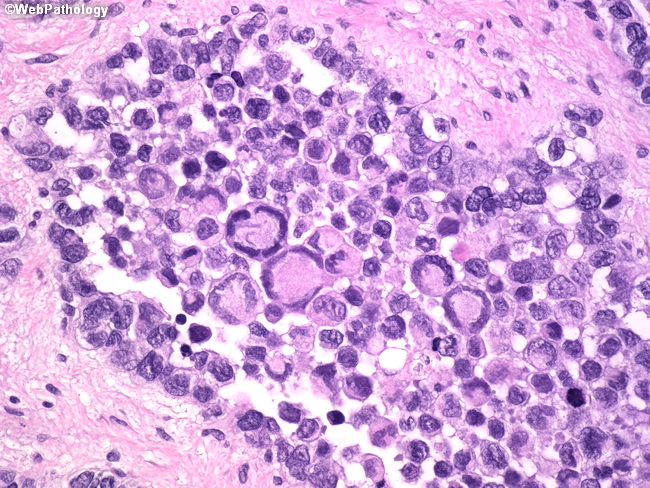

Soft Tissues: Alveolar Rhabdomyosarcoma

Webpathology.com: A Collection Of Surgical Pathology Images

rhabdomyosarcoma alveolar webpathology pathology

Webpathology.com: A Collection Of Surgical Pathology Images

rhabdomyosarcoma alveolar webpathology pathology comments microscopic

Alveolar Rhabdomyosarcoma; A. Typical Architecture With Pseudoalveolar

Webpathology.com: A Collection Of Surgical Pathology Images

rhabdomyosarcoma webpathology

Webpathology.com: A Collection Of Surgical Pathology Images

rhabdomyosarcoma alveolar webpathology